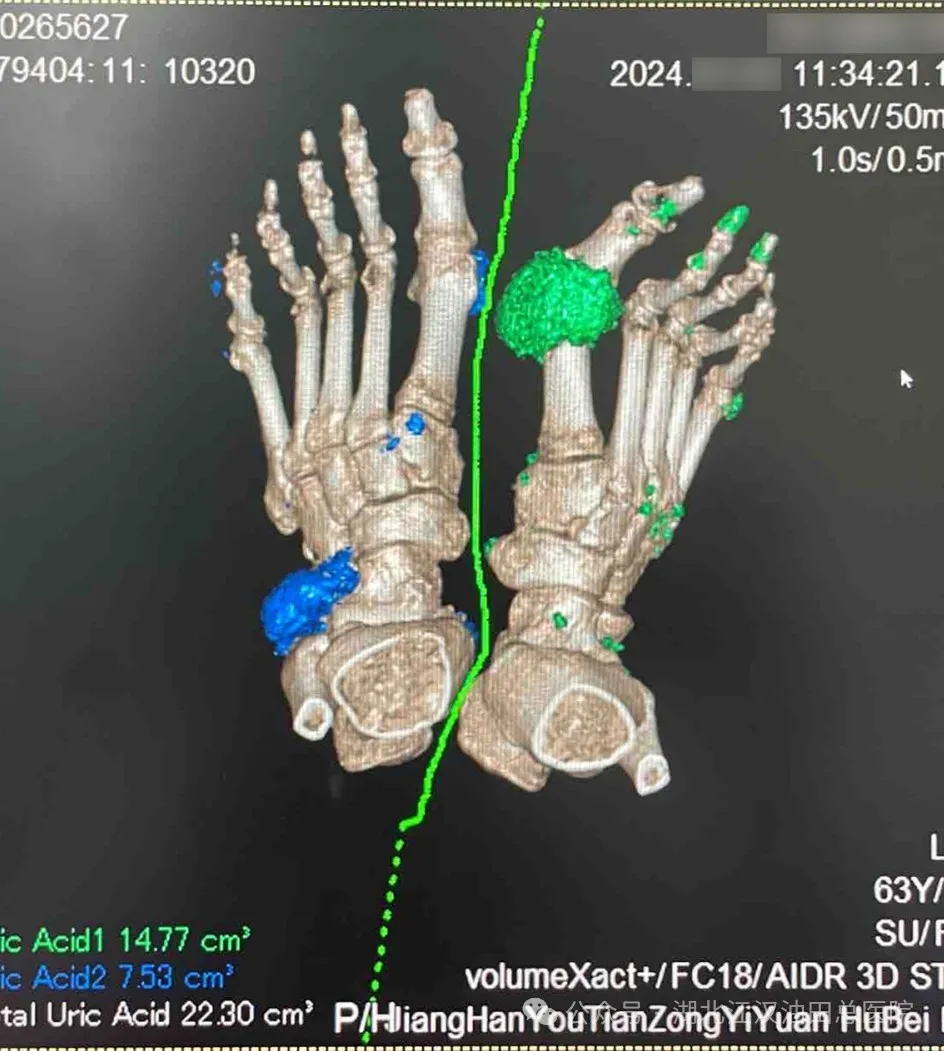

CT能谱扫描通过对尿酸盐结晶(痛风石)成像,不仅能清晰显示痛风石的形态、大小及位置,还能通过物质分析技术判断其成分,使得尿酸盐结晶的识别更加准确。有高尿酸血症,临床怀疑痛风结晶形成的患者,CT能谱扫描能为其提供有力的诊断;对于已确诊痛风的患者,CT能谱扫描也能通过对痛风石体积的连续定量检测来确认治疗效果。

CT能谱扫描在痛风结石形成初期就能进行检测,可以提高疾病的早期发现率,适合有不明原因关节疼痛或不典型部位疼痛的患者进行检查。